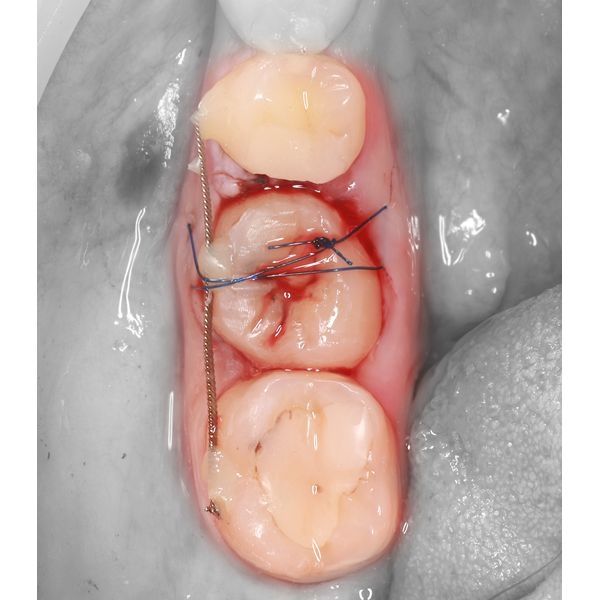

- специальными щипцами удалили зуб 2.8 и установили его на место зуба 4.6, после чего зафиксировали его ортодонтической проволокой-рейтейнером и жидкотекучим композитом;

Операция длилась около 30 минут.